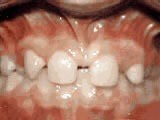

Patient started treatment at age 11 and wore braces for 26 months. He loves his new smile.